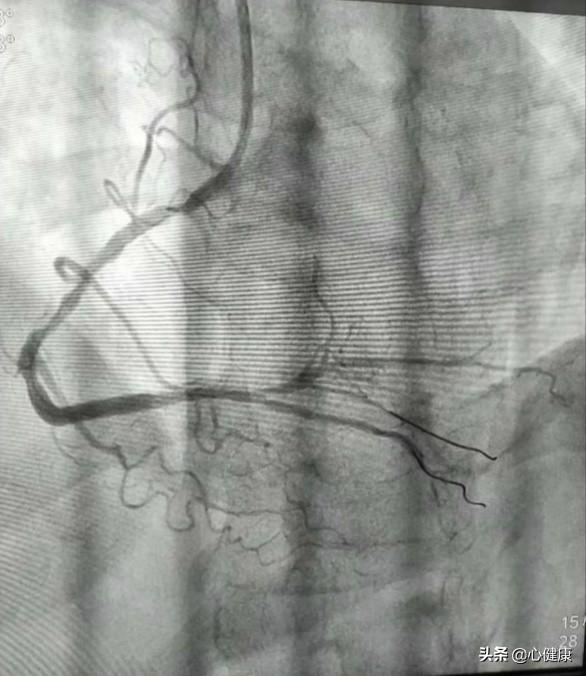

La coronarographie, en termes simples, est une ponction percutanée des artères superficielles du corps à l'aide d'un cathéter cardiaque. Celui-ci est souvent ponctionné dans l'artère radiale ou fémorale et remonte de manière rétrograde le long de l'artère pour pénétrer dans les portails de l'artère coronaire gauche ou droite, où un produit de contraste est injecté pour visualiser les artères coronaires.

En procédant de la sorte, la lumière de la principale artère coronaire gauche ou droite et de ses branches peut être clairement visualisée pour voir s'il existe des foyers sténosés dans les vaisseaux du système coronaire et pour déterminer l'étendue de la sténose. Une décision peut alors être prise quant au plan de traitement. Par exemple, une intervention, un pontage chirurgical ou un traitement médical conservateur. Ou même aucun traitement.

(2) Étapes spécifiques : le patient est allongé sur le lit d'opération dans le laboratoire de cathétérisme cardiaque, le site de l'opération est désinfecté (main ou cuisse), un anesthésique local est administré dans cette zone, un trou est pratiqué dans le vaisseau sanguin artériel à l'aide d'une aiguille, un fil-guide fin et un cathéter sont envoyés, et le cathéter à fil-guide peut atteindre les artères coronaires en suivant les vaisseaux sanguins sous le contrôle de la radiographie, puis un type de médicament (agent de contraste) est injecté dans la tête du cathéter fin, ce qui fera apparaître les vaisseaux sanguins sous les rayons X, et la taille, le trajet, l'obstruction n'est pas visible, les artères coronaires gauche et droite, chaque branche, etc. d'un seul coup d'œil. Les vaisseaux sanguins apparaissent sous la radiographie et l'on peut voir d'un seul coup d'œil leur taille, leur trajet, s'ils sont obstrués ou non, ainsi que les artères coronaires gauche et droite et les différentes branches des artères. Si le problème n'est pas grave, c'est la fin, on retire le cathéter, on ponctionne le poignet à l'aide d'un compresseur pour éviter les saignements. L'ensemble du processus prend 10 à 30 minutes si vous êtes compétent. Si le problème est grave, le traitement (dilatation par ballonnet, pose d'un stent, etc.) peut se poursuivre et prendre plus de temps.

présent .Plus de 95 % des patients partent de l'artère radiale du poignet.Le médecin insère un tuyau de l'artère radiale dans l'ouverture de l'artère coronaire et l'envoie dans l'ouverture de l'artère coronaire de notre cœur, puis il ouvre le produit de contraste et l'irradie avec des rayons X, de sorte que les vaisseaux sanguins du cœur peuvent être clairement vus, et notre médecin, en observant le développement de l'image, peut juger si les artères du cœur sont rétrécies, si elles sont obstruées ou non, et, si elles sont obstruées, à quel point le sont-elles ? À partir de là, nous pouvons déterminer si nous souffrons d'une maladie coronarienne ou d'autres maladies cardiaques !

Il existe des angiographies coronaires et des angiographies cardiaques (auriculaires et ventriculaires). La coronarographie consiste à utiliser un cathéter fin comme un cheveu le long de l'artère radiale (au niveau du poignet) ou de l'artère fémorale (au niveau de la cuisse) pour prolonger l'entrée artificielle jusqu'à l'ouverture de l'artère coronaire du cœur, puis à injecter l'agent de contraste (dans les rayons X) dans les artères coronaires, afin de montrer la morphologie interne des artères coronaires, par exemple pour vérifier l'absence de rétrécissement des artères coronaires, de plaque, etc. L'objectif principal est de comprendre la forme interne des artères coronaires et la vitesse du flux sanguin dans les artères coronaires.

Il s'agit d'une ponction de l'artère radiale de la main ou de l'artère fémorale à la racine de la cuisse, le cathéter sera envoyé le long des vaisseaux sanguins artériels, a été étendu aux artères coronaires, injecté dans l'agent de contraste, l'agent de contraste sera mélangé à nos artères coronaires du sang, rempli avec les artères coronaires, les vaisseaux sanguins dans la radiographie n'est pas visible, mais après l'injection de l'agent de contraste, peut être visible sous la radiographie, nous serons en mesure d'observer la situation des vaisseaux sanguins pour voir la situation des blocages, de la sténose, de la plaque ! Nous pouvons alors examiner le vaisseau sanguin pour voir s'il y a un blocage, un rétrécissement ou une plaque !